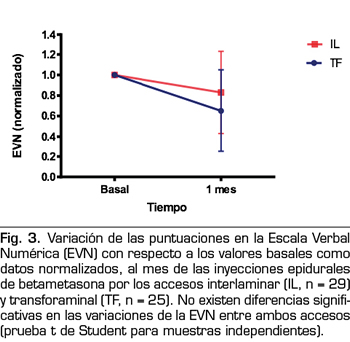

Un total de 64 pacientes con lumbociatalgia unilateral fueron incluidos en el estudio en el periodo de enero del 2016 a noviembre del 2017. De ellos, 29 fueron tratados con inyecciones epidurales de esteroides por vía interlaminar parasagital, mientras que 25 fueron tratados utilizando el abordaje transforaminal. Diez pacientes que recibieron el tratamiento no volvieron al control (3 por vía interlaminar parasagital, 7 por vía transforaminal). La edad promedio de los pacientes fue de 51 años. En cuanto al sexo, 32 pacientes eran de sexo femenino y 8 de sexo masculino. El tiempo promedio de evolución del dolor fue de 29 meses. La totalidad de los pacientes presentaron en la resonancia magnética protrusiones discales en los espacios L4/L5 y L5/S1, con grados variables de estenosis del canal. No se trataron pacientes con hernias discales. De los 54 pacientes, 29 fueron tratados con betametasona por la vía interlaminar parasagital y 25 por la vía transforaminal. La betametasona administrada por la vía interlaminar parasagital redujo la puntuación en la EVN un 20 %, de 7,7 ± 1,5 a 6,2 ± 3,1 (diferencia estadísticamente significativa, p = 0,03, prueba t de Student para muestras pareadas) y por la vía transforaminal un 36 %, de 8,3 ± 1,5 a 5,3 ± 3,3 (p = 0,0001). La Figura 3 muestra los valores de la EVN normalizados (esto es, expresados como porcentaje de cambio) de ambos grupos, basales y al mes del tratamiento. Si bien se puede observar que el porcentaje de cambio es mayor en los pacientes en los que se utilizó la vía transforaminal que en los que se utilizó el abordaje interlaminar, esta diferencia no es estadísticamente significativa (p = 0,13, prueba t de Student para muestras independientes).